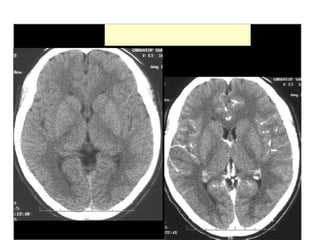

Effects of a complete MCA stroke

• The hallmarks of an MCA stroke are the focus of most

public-awareness messages and prehospital stroke

assessment tools—facial asymmetry, arm weakness, and

speech deficits. Complete MCA strokes typically cause:

• hemiplegia (paralysis) of the contralateral side, affecting

the lower part of the face, arm, and hand while largely

sparing the leg

• contralateral (opposite-side) sensory loss in the same areas

• contralateral homonymous hemianopia—visual-field

deficits affecting the same half of the visual field in both

eyes.

Effects of acomplete MCA stroke • The hallmarks of an MCA stroke are the focus of most public-awareness messages and prehospital stroke assessment tools—facial asymmetry, arm weakness, and speech deficits. Complete MCA strokes typically cause: • hemiplegia (paralysis) of the contralateral side, affecting the lower part of the face, arm, and hand while largely sparing the leg • contralateral (opposite-side) sensory loss in the same areas • contralateral homonymous hemianopia—visual-field deficits affecting the same half of the visual field in both eyes.